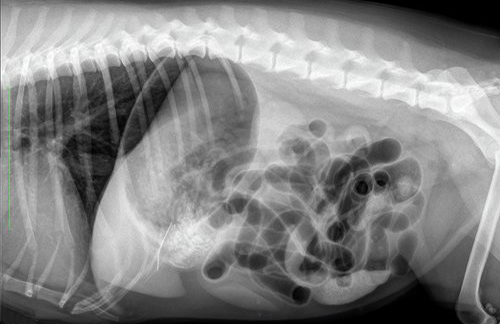

Het verhaal begint op het vakantieadres op Texel. Lady krijgt klachten van diarree, braken en ze is erg ziek. Bij de dierenarts worden vervolgens röntgenfoto’s gemaakt. Het is de verdenking dat ze ziek is geworden door het drinken van zeewater en het zand dat ze heeft binnengekregen, maar er is nog iets anders te zien; een langwerpige structuur.

Het baasje van Lady vindt het fijn als zijn eigen dierenarts ook naar de röntgenfoto’s kijkt en stuurt de foto’s naar ons. We staan zelf ook even te kijken over wat er op de foto te zien is. Ondertussen knapt Lady behoorlijk op en komt de eigenaar naar huis.

Ter controle, of de structuur nog in de buik aanwezig is, worden opnieuw röntgenfoto’s gemaakt. Hierop is het voorwerp nog goed zichtbaar, met een soort oogje erin. Het moet dus een naald zijn. De foto’s suggereren verder dat de naald niet in het maag-darmstelsel zit, maar in de buikholte.